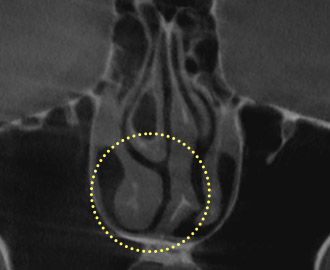

Hypertrophic

Rhinitis

Hypertrophic rhinitis

occurs when

inflammation

in the nasal mucosa,

called

the “inferior turbinate,”

causes it

to enlarge,

leading to symptoms such

as nasal congestion and

olfactory

disorders.

Treatment Points

Use a radiofrequency

device to

shrink the

enlarged mucosa

to its

normal size, restoring

normal

breathing.

Precision Nasal Endoscopy

Precision nasal endoscopy is performed before surgery to directly

observe internal nasal structures, as 3D-CT provides an overview

for functional nasal surgery.

It is an examination performed before surgery to

directly observe the internal nasal structures and

accurately assess conditions that are difficult to

identify with 3D-CT, such as the state of the nasal

mucosa, polyps, nasal polyposis, and postnasal

drip inflammation.